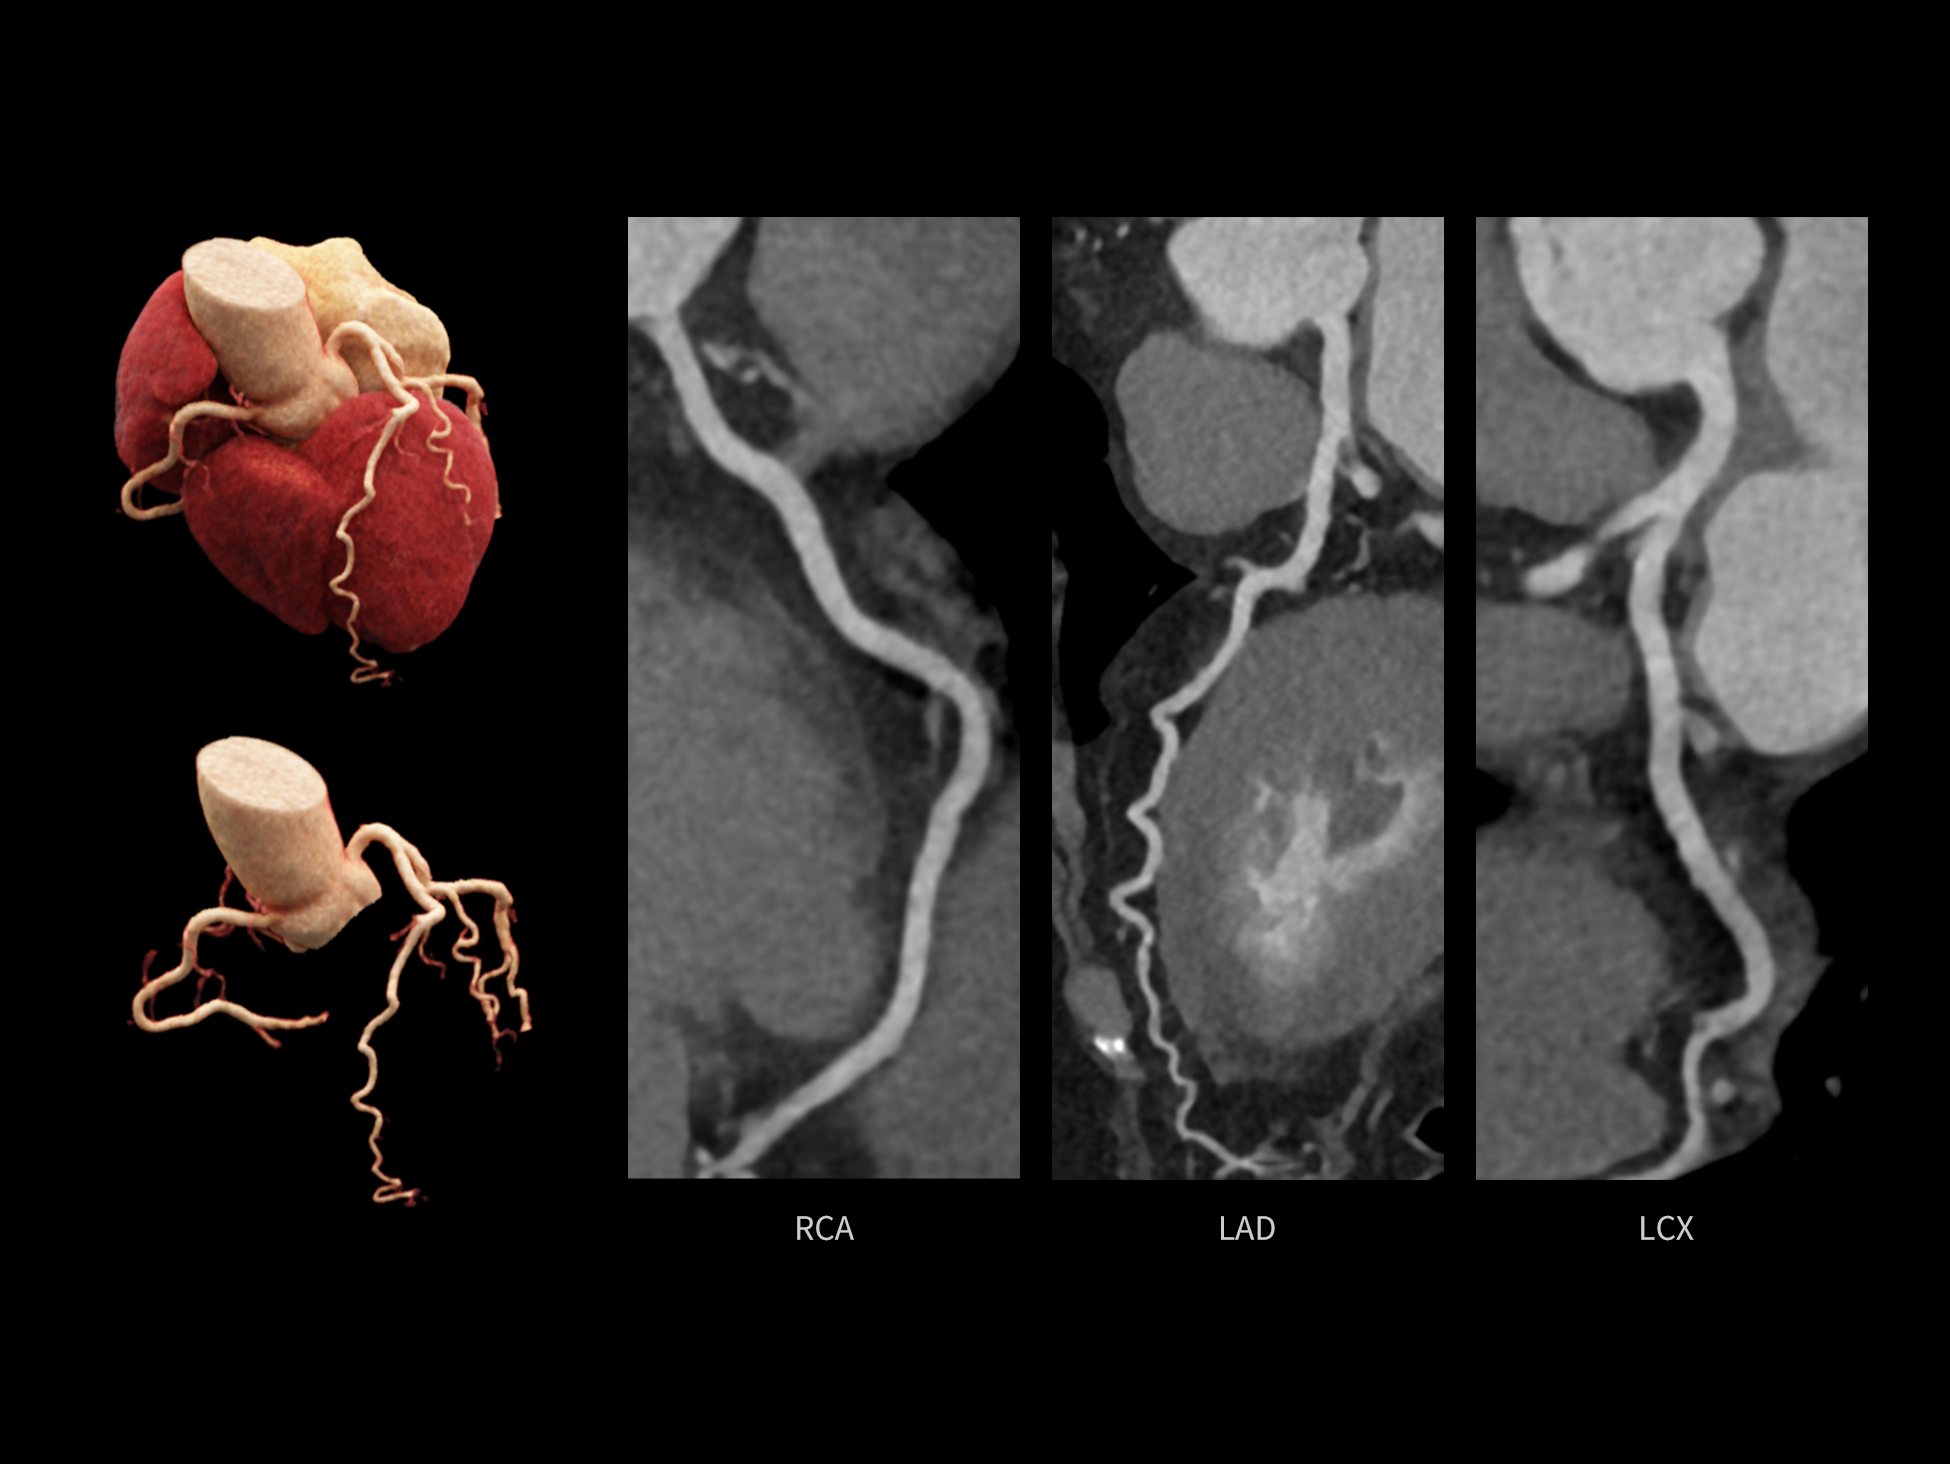

uCT SiriuX® 挑战心脏成像时间分辨率的极限,精准捕捉心脏全周期的动态变化。无论静态解剖形态,还是动态功能表现,都能清晰呈现,让心脏不再是“定格”的器官,而成为可视的生命律动。

突破全心时间分辨率极限

CardioCapture 2.0 通过“识别–追踪–建模–校正”的完整流程,精准分割心脏结构,动态追踪运动轨迹,并构建多时相运动场,最终实现冠脉、瓣膜、心肌及心室结构的同步校正,清晰洞见每一次心跳细微变化,真正将心脏动态掌握于毫秒之间。

心脏成像,自由掌控